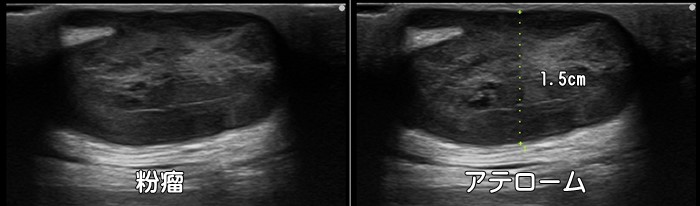

粉瘤・アテローム

背部にできた小さな腫瘤。表在性で境界明瞭で底面後方エコーの増強がみられ粉瘤を疑います。ガングリオンの場合は内部は著明な低エコー像ですが、粉瘤はやや高エコー像に描出されます。

“しこり”や“こぶ”は悪性の腫瘍の場合もありますので、表在性 or 深在性・輪郭が整 or 不整・嚢胞性 or 充実性・内部が均一 or 不均一・大きさは5cm以上

or 以下・血流信号の有無・可動性の有無・痛みの有無などを評価する必要があります。